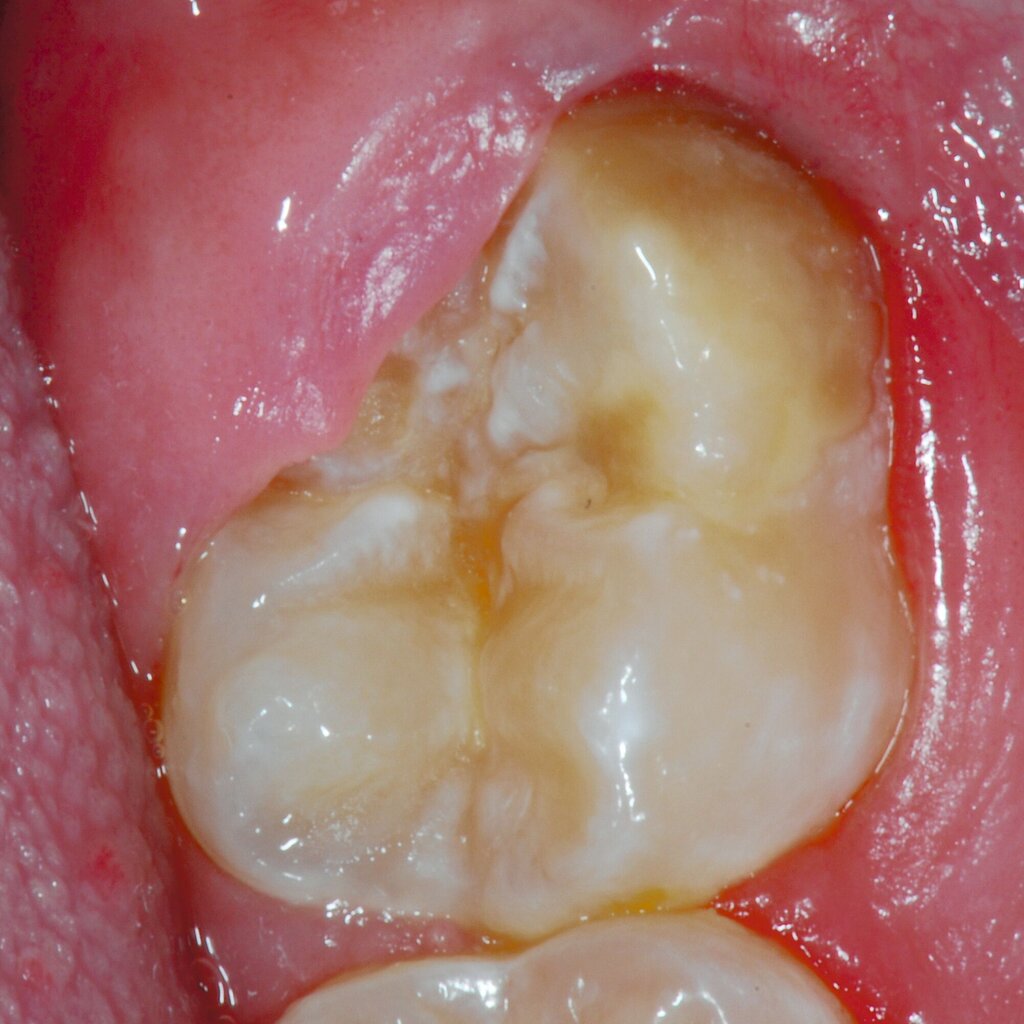

An umfangreich hypomineralisierten Zähnen können Schmelzeinbrüche (engl.: „enamel breakdown“ oder „enamel desintegration“, Abbildung 5) auftreten [Lygidakis et al., 2010; 2022]. Da diese oftmals die Folge einer fehlenden Belastungsfähigkeit des Zahnschmelzes sind und erst nach der Einstellung der Zähne in die Okklusion auftreten, werden sie auch als posteruptive Schmelzeinbrüche bezeichnet. Sie sind häufig im Bereich der Kauflächen beziehungsweise Höcker der Molaren zu finden, führen zur Dentinexposition und damit einhergehend zu ausgeprägten Hypersensitiven insbesondere bei Kindern, deren Zähne gerade erst durchgebrochen sind [Linner et al., 2021].

Bei post- beziehungsweise präeruptiven Oberflächendefekten ergibt sich in einigen Fällen die Indikation zur Restauration dieser MIH-Zähne. Unter Verweis auf die Lokalisation von MIH-bedingten Hypomineralisationen außerhalb der typischen Kariesprädilektionsstellen – zum Beispiel okklusale Fissuren und Grübchen oder Approximalflächen – werden diese als „atypische Restaurationen“ (engl.: „atypical restoration“, Abbildung 6) klassifiziert. Als ein weiteres Erkennungsmerkmal gilt die Präsenz von Hypomineralisationen im Bereich der Restaurationsränder. MIH- und kariesbedingte Restaurationen können und sollten sicher voneinander abgegrenzt werden.

Für die Dokumentation und Klassifikation der MIH wurden verschiedene Systeme vorgeschlagen. Als historisch und veraltet gilt der (modifizierte) DDE-Index. Demgegenüber haben die Kriterien der EAPD – abgegrenzte Opazitäten (Abbildung 3 und 4), Schmelzeinbrüche (Abbildung 5), atypische Restaurationen (Abbildung 6) – mittlerweile die weiteste Verbreitung gefunden. Diese wurden 2003 erstmals zur Beschreibung der MIH auf empirischer Basis publiziert [Weerheijm et al., 2003] und den Jahren 2010 und 2022 im Rahmen der damaligen MIH-Workshops bestätigt [Lygidakis et al., 2010; 2022].